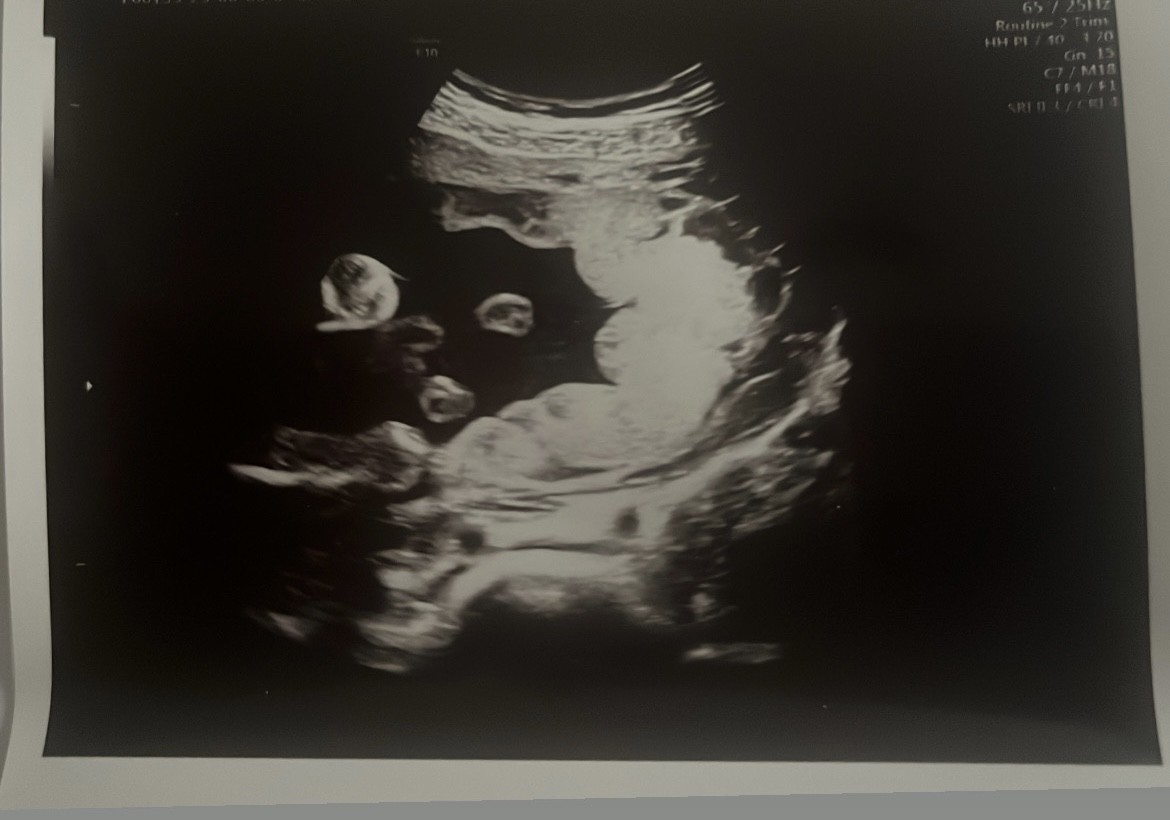

Połówkowe 21 tc chłopak czy dziewczyna ?

Dziewczyny co sądzicie ? Czy to jest zdjęcie nocnikowe na którym widać płeć ?

zdziwiłam się, bo na jednej z fejsbukowych zagranicznych grup wstawiłam to zdjęcie z potwierdzeniem dziewczynki, a trzy osoby napisały mi ze na 100% nie jest to tzw potty shot i nie widać płci 🤯 Ogólnie ufałabym lekarzowi gdyby dziecko nie leżało plecami do nas, jestem w szoku i czekam na kolejna wizytę. Poniżej macie screeny